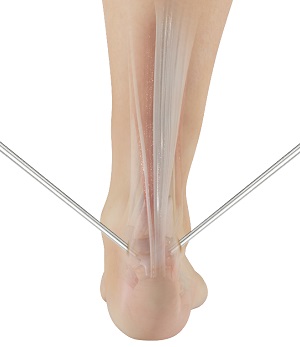

Minimally Invasive Achilles Repair

Minimally invasive Achilles repair is a surgical technique used to treat a tear or rupture of the Achilles...